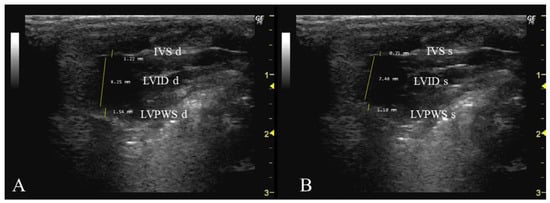

- How to measure IVS, LVID, and LVPW